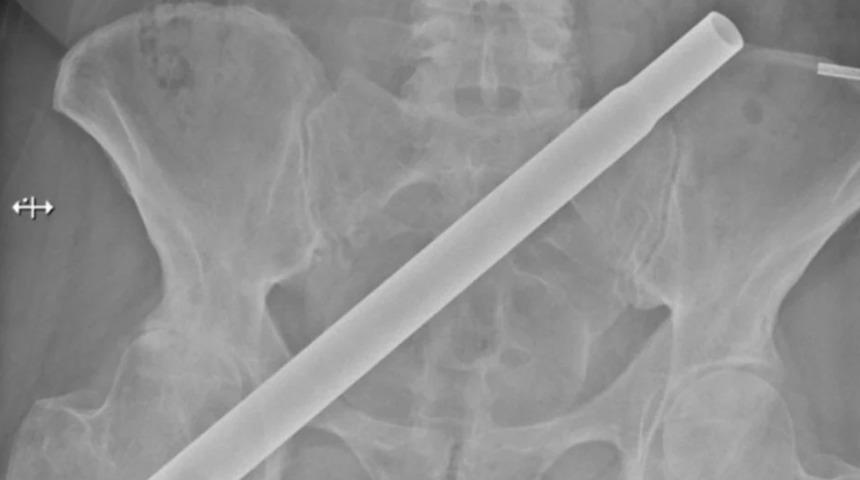

Ağacın üst kısımlarını süslemek için bir sandalyeye çıkan kadın dengesini kaybedince düştü. Düşerken metal çubuk leğen kemiğine saplandı. Kadının pelvisinin bir röntgeni, metal çubuğun pelvise sağdan çapraz olarak sol tarafa doğru girdiğini gösteriyor.